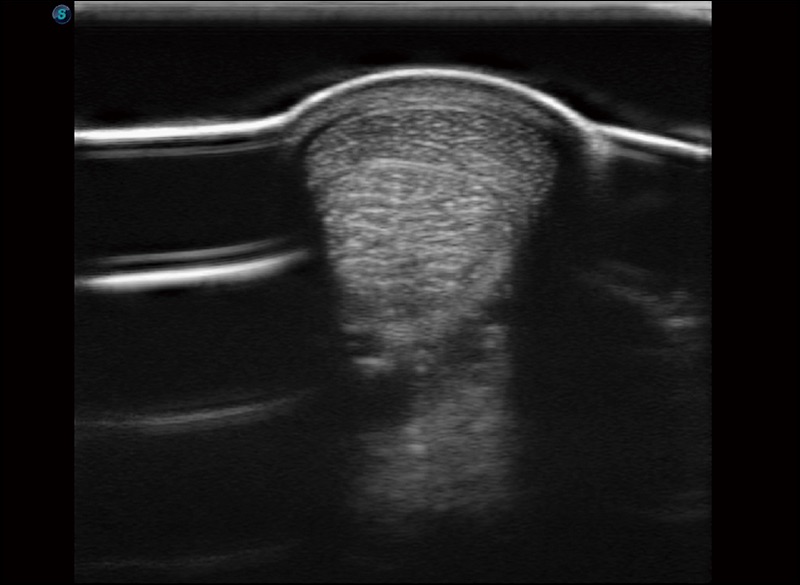

支持线阵和凸阵探头,一键操作即可获得更宽的图像视野

实时宽景成像

可实时观察感兴趣区域和病变位置